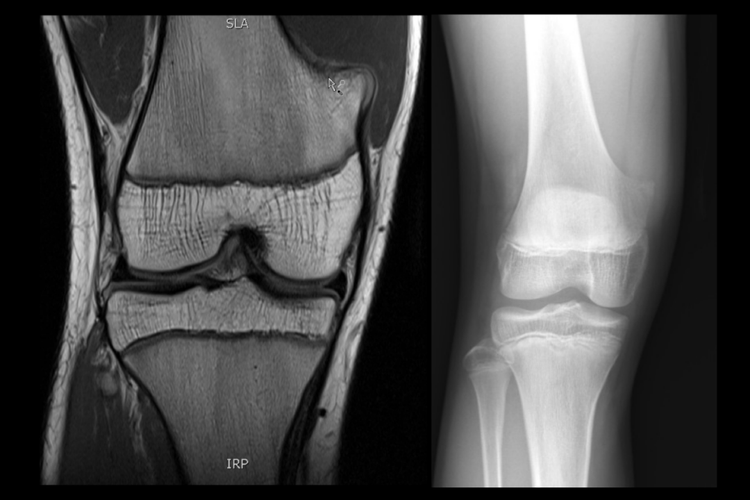

小孩子膝盖内侧骨头突出者可通过体格检查、X线等检查明确诊断,以便于后续治疗。

正常骨性突出:小孩子膝关节由股骨下端、胫骨上端和髌骨构成,膝盖内侧本就有胫骨内侧髁、股骨内侧髁等骨性结构,可表现出膝盖内侧骨头突出。

X型腿:又称为膝外翻,小孩可有患侧膝关节周围压痛、膝盖内侧骨头突出等,双侧膝外翻者步态蹒跚,行走时双膝内侧互碰,单侧畸形者则跛行、步态异常、易跌倒。平卧位两膝并拢时,两内踝显著分开。两踝间距离长度表示膝外翻的程度。严重膝外翻导致股四头肌力线外移,Q角增大,髌骨易出现向外脱位。

骨软骨瘤:小孩膝盖处有骨软骨瘤时,膝关节周围可出现生长缓慢、无痛性、质硬的包块,表现为小孩子膝盖内侧骨头突出。部分患者剧烈活动时或疲劳活动后有患部疼痛、酸胀不适。较大或较浅部位的包块对外观有一定影响,包块长时间对周围软组织产生摩擦、压迫,可引发滑囊炎而出现疼痛感。